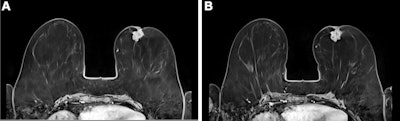

"This is the ideal contrast agent for healthy people who will predictably require repetitive contrast agent injections such as women with extremely dense breast tissue who undergo breast MRI for screening," Kuhl told AuntMinnieEurope.com. "This is where I see the most important use of this new contrast agent."

Kuhl's group compared the performance of gadobutrol to gadopiclenol for lesion evaluation via a study that included 260 participants who underwent both gadopiclenol- and gadobutrol-enhanced MRI and had at least one identified lesion. Most patients presented with neoplasms (66%), and the most frequent of these were liver metastases and breast cancer.

The gadopiclenol exam was performed with 0.05 mmol/kg of contrast, while the gadobutrol exam was performed with 0.1 mmol/kg. The exams were read by 18 readers divided into three reading groups to compare the two contrast agents.

The investigators found that gadopiclenol at half the dose of gadobutrol performed comparably for all qualitative visualization parameters and for all readers. The majority of readers across the three groups (ranging from 75% to 83%) reported no preference between the two agents for image quality.